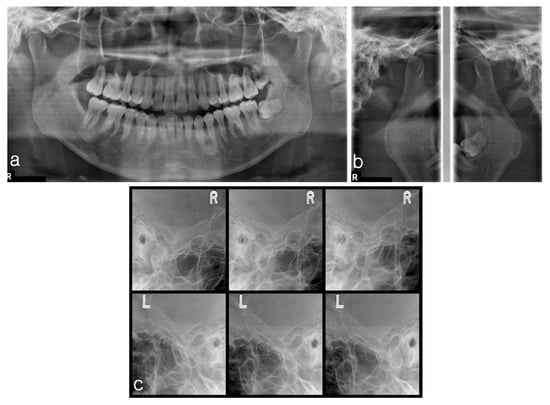

2.1.2. Imaging

2.2.2. Imaging